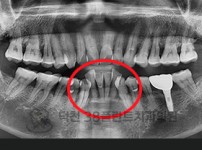

치료전후